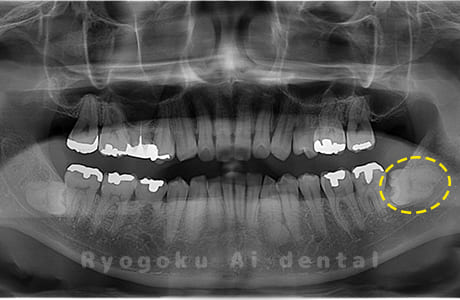

Case09

- 原因

- 下顎左の水平埋伏智歯

- 治療内容

- 下顎左の水平埋伏智歯を抜歯したケースです。

<リスク・副作用>

手術後は痛み、腫れ、痺れなどの副作用が生じる場合があります。